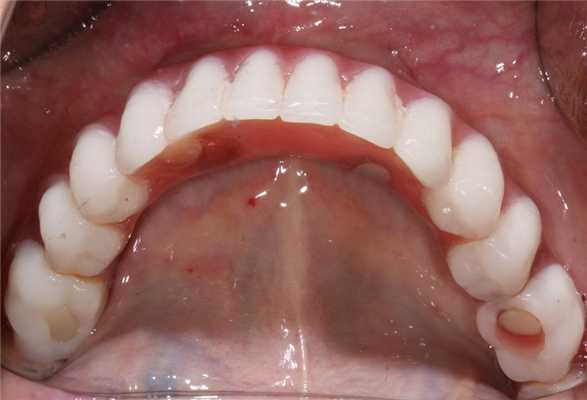

Через 6 месяцев после операции первичные адаптационные протезы были заменены на новые адаптационные протезы с армированием (фото 18, 19, 20, 21, 22). Фотографии выполнены через 8 месцев после функционирования второго адаптационного протеза. На снимках видно достаточное количество прикрепленной слизистой, которое удалось создать благодаря правильному позициониравнию имплантатов и естественному заживлению после удаления (фото 23, 24).